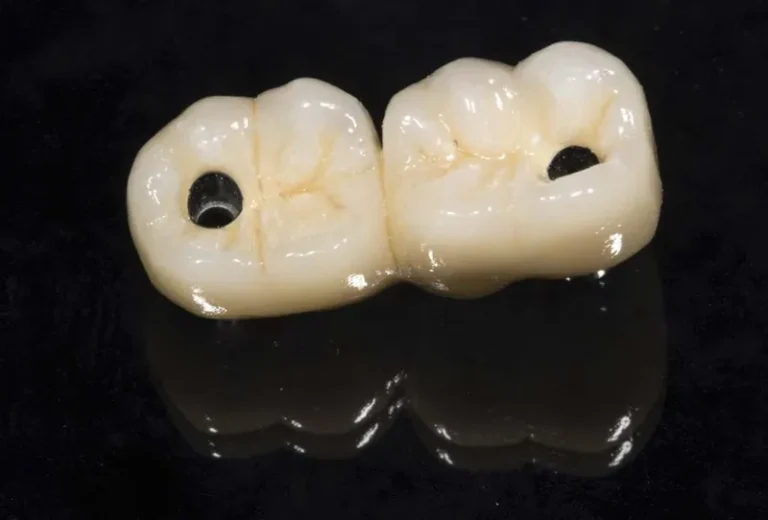

Las diferencias entre implante dental y puente dental son fundamentales para elegir el tratamiento más adecuado. El implante dental consiste en un tornillo de titanio que se inserta en el hueso maxilar, reemplazando la raíz del diente perdido, mientras que el puente dental se apoya en los dientes adyacentes para sostener la prótesis. Aunque ambas…

La elección de una marca de implantes dentales es crucial para garantizar el éxito del tratamiento y la satisfacción del paciente a largo plazo. Las mejores marcas de implantes dentales se distinguen por su riguroso proceso de fabricación, respaldo científico y trayectoria en el mercado. Empresas como Straumann, Nobel Biocare y Zimmer Biomet lideran la…